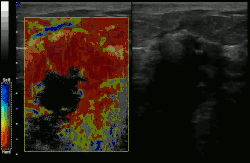

![]() Conventional ultrasonography (lower image) and elastography (supersonic shear imaging; upper image) of papillary thyroid carcinoma, a malignant cancer. The cancer (red) is much stiffer than the healthy tissue. | |

Supersonic shear imaging (SSI)

Supersonic shear imaging (SSI)[8][9] gives a quantitative, real-time two-dimensional map of tissue stiffness. SSI is based on SWEI: it uses acoustic radiation force to induce a 'push' inside the tissue of interest generating shear waves and the tissue's stiffness is computed from how fast the resulting shear wave travels through the tissue. Local tissue velocity maps are obtained with a conventional speckle tracking technique and provide a full movie of the shear wave propagation through the tissue. There are two principal innovations implemented in SSI. First, by using many near-simultaneous pushes, SSI creates a source of shear waves which is moved through the medium at a supersonic speed. Second, the generated shear wave is visualized by using ultrafast imaging technique. Using inversion algorithms, the shear elasticity of medium is mapped quantitatively from the wave propagation movie. SSI is the first ultrasonic imaging technology able to reach more than 10,000 frames per second of deep-seated organs. SSI provides a set of quantitative and in vivo parameters describing the tissue mechanical properties: Young's modulus, viscosity, anisotropy.

This approach demonstrated clinical benefit in breast, thyroid, liver, prostate, and musculoskeletal imaging. SSI is used for breast examination with a number of high-resolution linear transducers.[10] A large multi-center breast imaging study has demonstrated both reproducibility[11] and significant improvement in the classification[12] of breast lesions when shear wave elastography images are added to the interpretation of standard B-mode and Color mode ultrasound images.